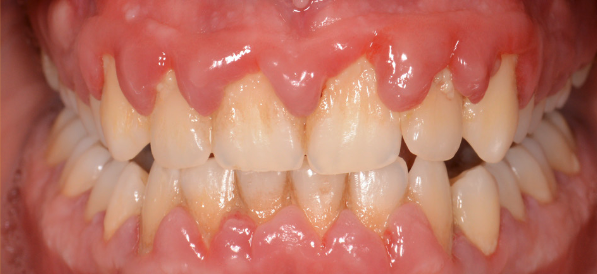

Cel mai vulnerabil punct al parodonțiului este șanțul gingival, ce se află la baza dintelui, între acesta și marginea gingivală liberă. Placa bacteriană și tartrul neîndepărtate corect printr-o igienă riguroasă se acumulează la acest nivel și reprezintă cauza declanșatoare a unei inflamații parodontale. Trebuie de asemenea înțeles de ce placa bacteriană are un efect distructiv asupra țesuturilor dentare: o parte din bacteriile prezente în cavitatea orală ce au ca principal suport nutritiv resturile alimentare îndepărtate prin periaj secretă o serie de toxine ce atacă suportul biologic al gazdei. (Fig. 5.1.1 și 5.1.2)

În cazul apariției oricărui tip de sângerare gingivală, pacientul este sfătuit să se adre- seze medicului parodontolog. Gingivita, fiind prima etapă inflamatorie din parcursul bolii parodontale, este complet reversibilă, atât timp cât este identificată precoce. (Fig. 5.1.3, 5.1.4)